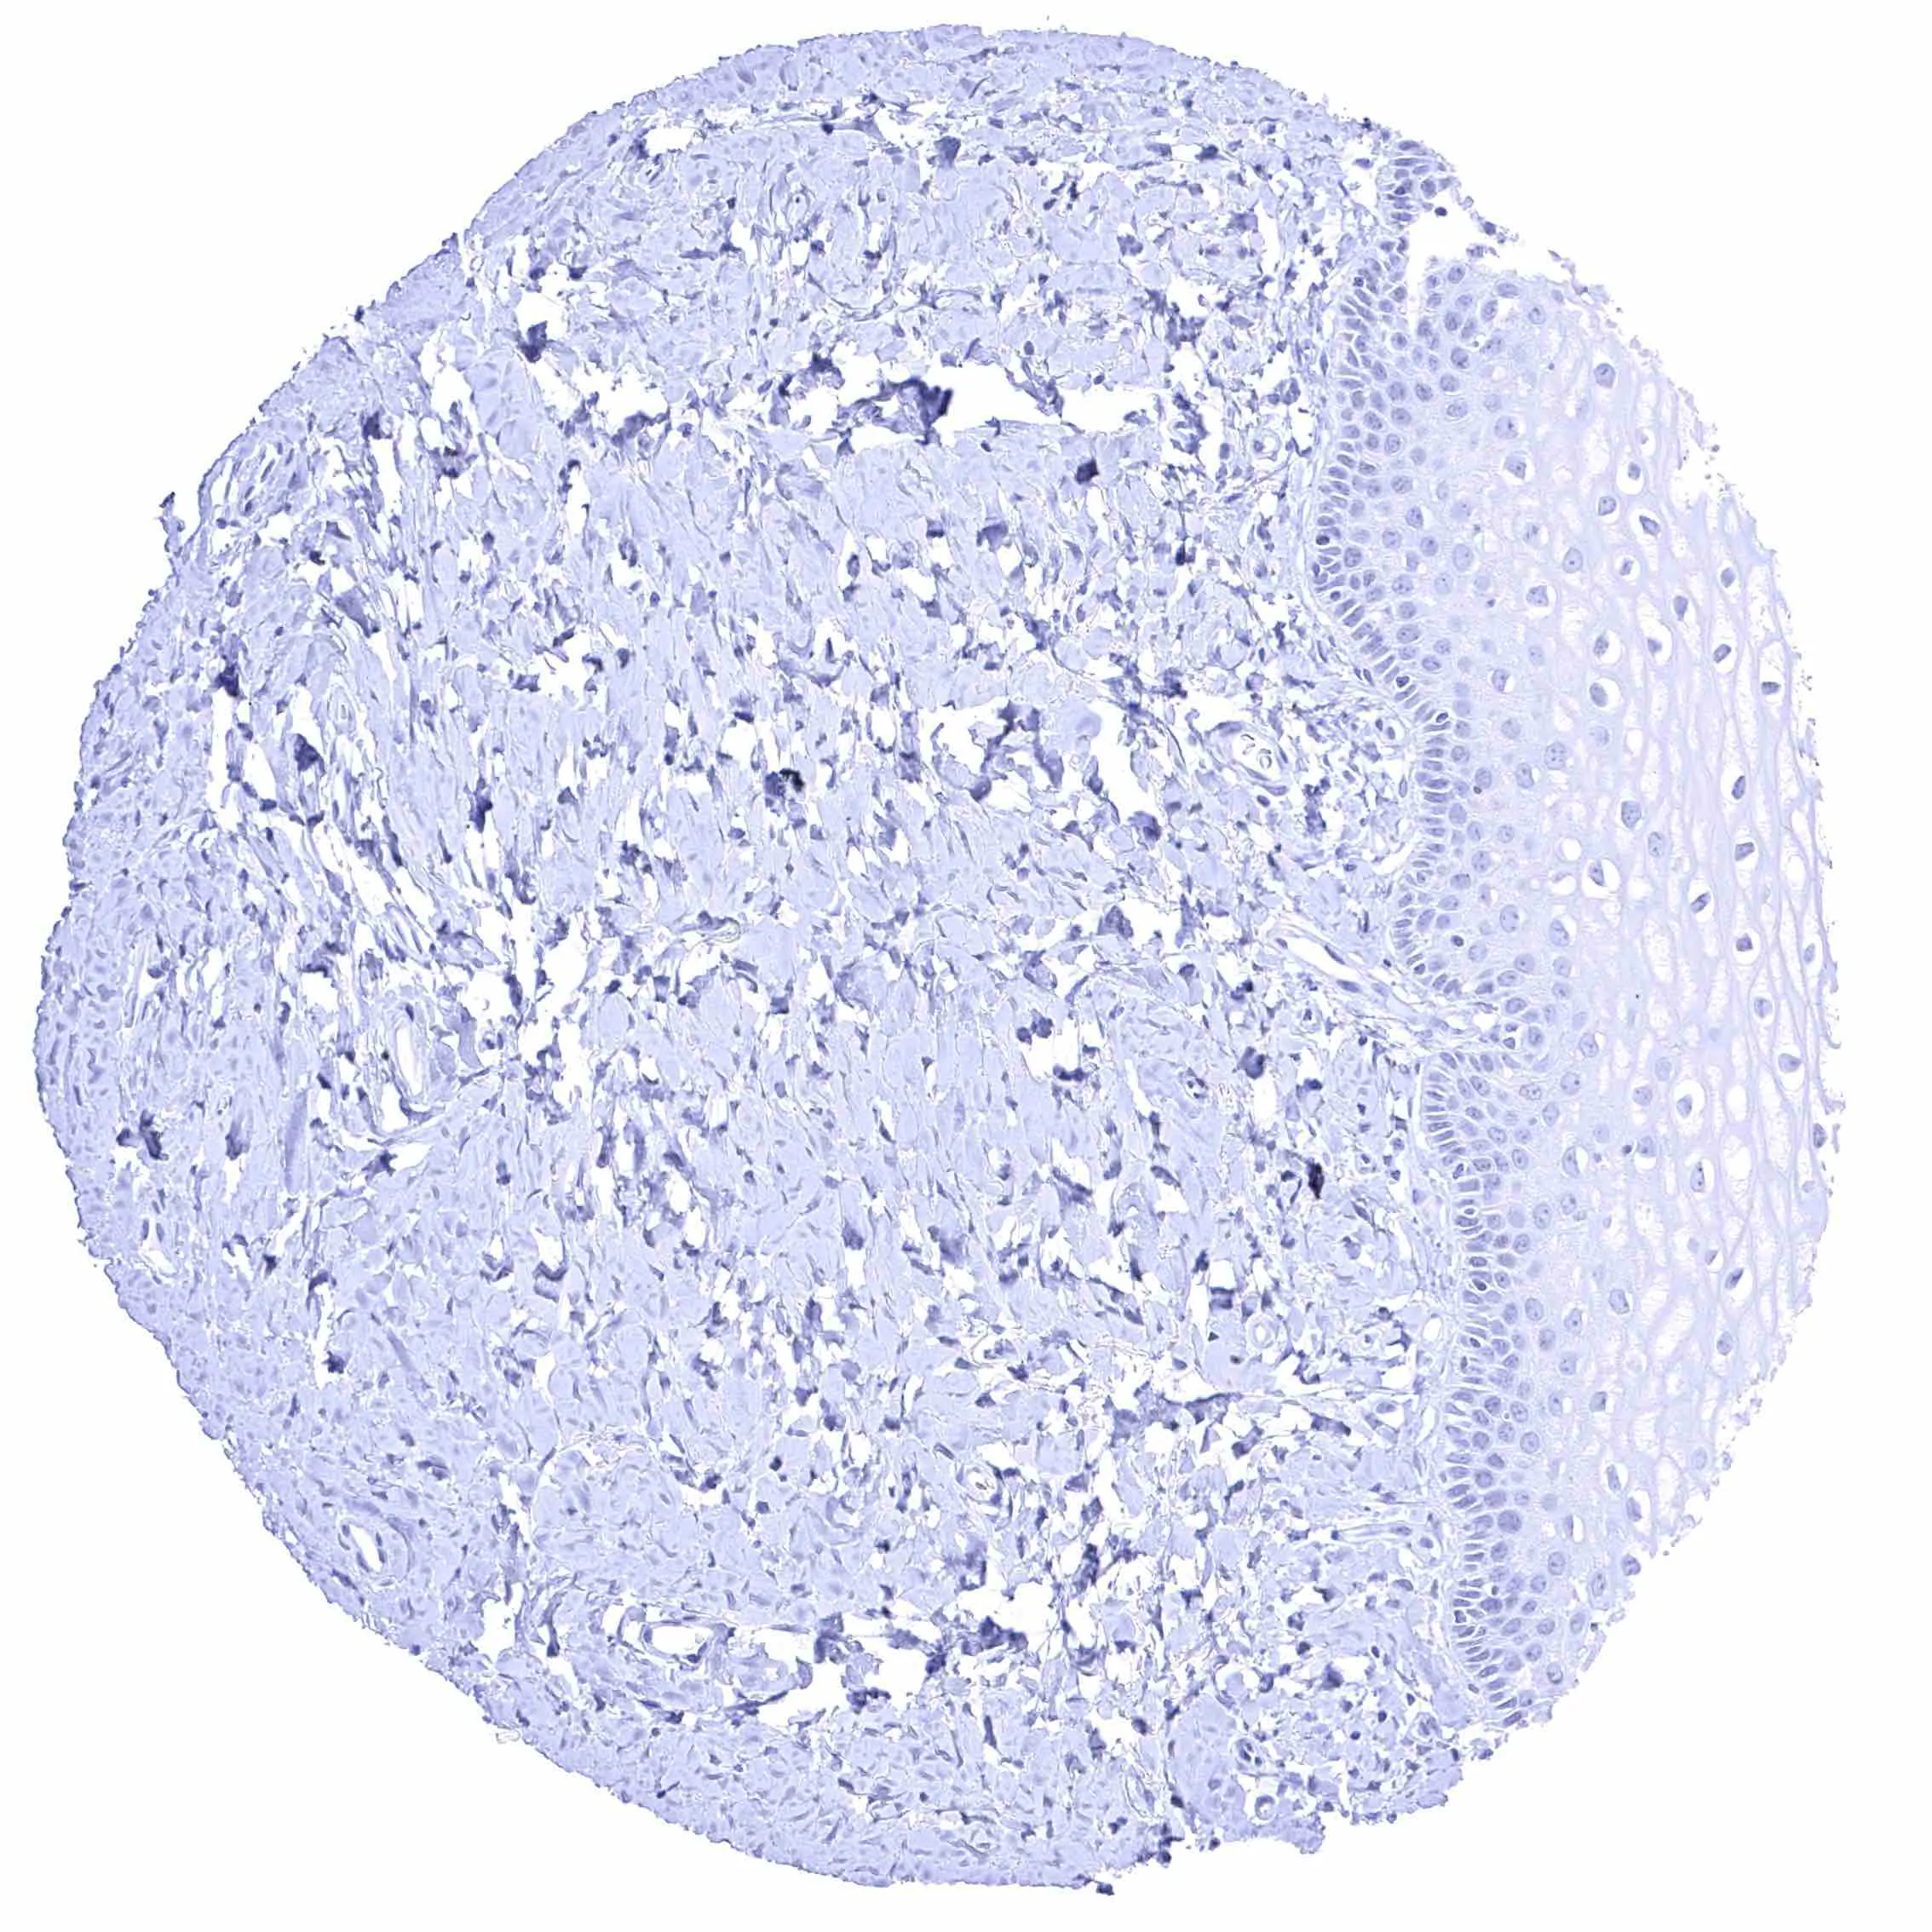

Urinary bladder, muscular wall

Urinary bladder, urothelium